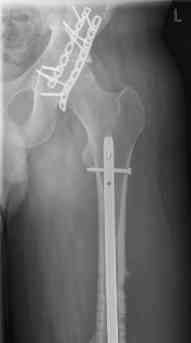

16 yr old boy, high energy motorcycle trauma trauma in July 2005 with:

- hip dislocation + acetabular fracture L

- distal femoral fracture L

- tibial shaft fracture L

- metatarsal fractures L

july 05: LISS femur, LCP plate tibia, double recon. plate post. acetabulum

feb 07: retrograde nail + bone graft + BMP